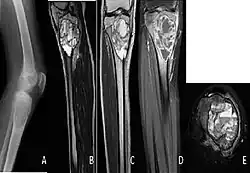

| A. X-ray: osteolytic lesion in tibia near knee. B/C/D/E. MRI with E showing fluid levels. | |

The cause is unknown.[1] Diagnosis involves medical imaging.[1] CT scan and X-ray show lytic expansion lesions with clear borders.[1] MRI reveals fluid levels.[1]

X-ray and CT scan show lytic expansion lesions with clear borders.[1] Expansion of cortex gives the lesion a balloon-like appearance. Larger lesions may appear septated.[11] MRI reveals fluid levels.[1] Bone scan shows outer radiotracer uptake, with a central dark area.[1][11]